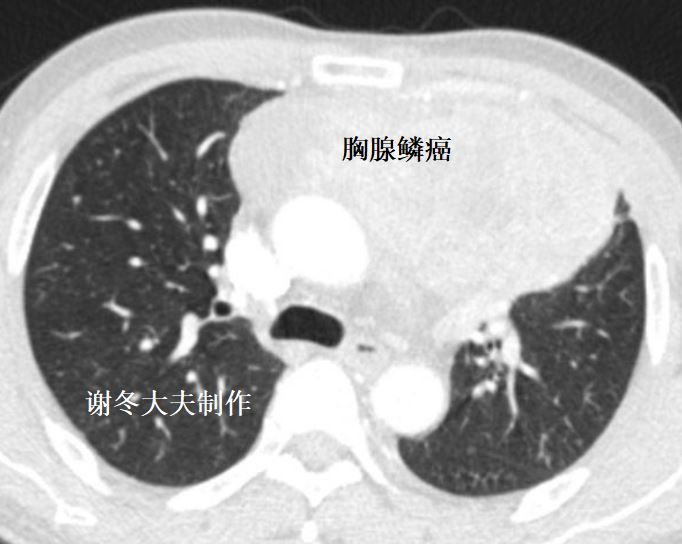

3. 胸腺癌

胸腺鳞癌